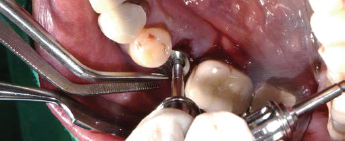

제조사의 식립 순서에 맞춰 Drilling 후 Fixture 식립

Fixture에 Volume Up Healing Abutment 체결

Easy Seal 등과 같은 수복재로 Screw Hole을 충전